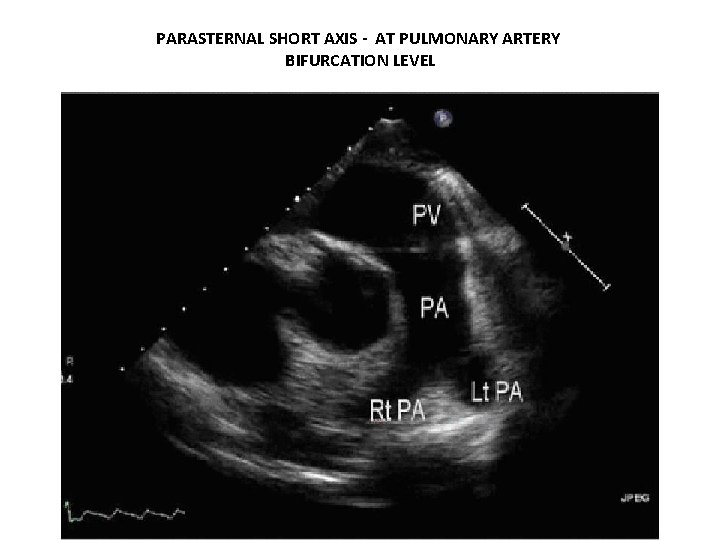

PARASTERNAL SHORT AXIS - AT PULMONARY ARTERY BIFURCATION LEVEL